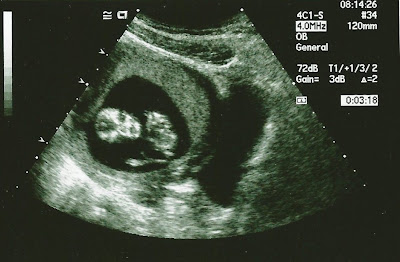

When was the baby's first picture?

At my first prenatal appointment we had a sonogram before the actual appointment. I was so excited to finally SEE our little one!

The sonogram showed our sweet little baby...although at the time I thought it looked more like a gummy bear! :-)